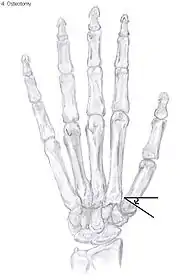

Showing the bones of the hand

Osteotomy of the thumb

Metacarpal osteotomy

The aim of metacarpal osteotomy is to change the pressure distribution on the TMC joint. The hope is that this will slow the pace of development of osteoarthritis. There is no evidence that this procedure can modify the natural course of TMC OA. Osteotomy may be considered for people with mild arthritis.[24]

During osteotomy, the metacarpal is cut and a wedge shape bone fragment is removed to move the bone away from the hand.[36] Postoperative, the thumb of the patient is immobilized using a thumb-cast.